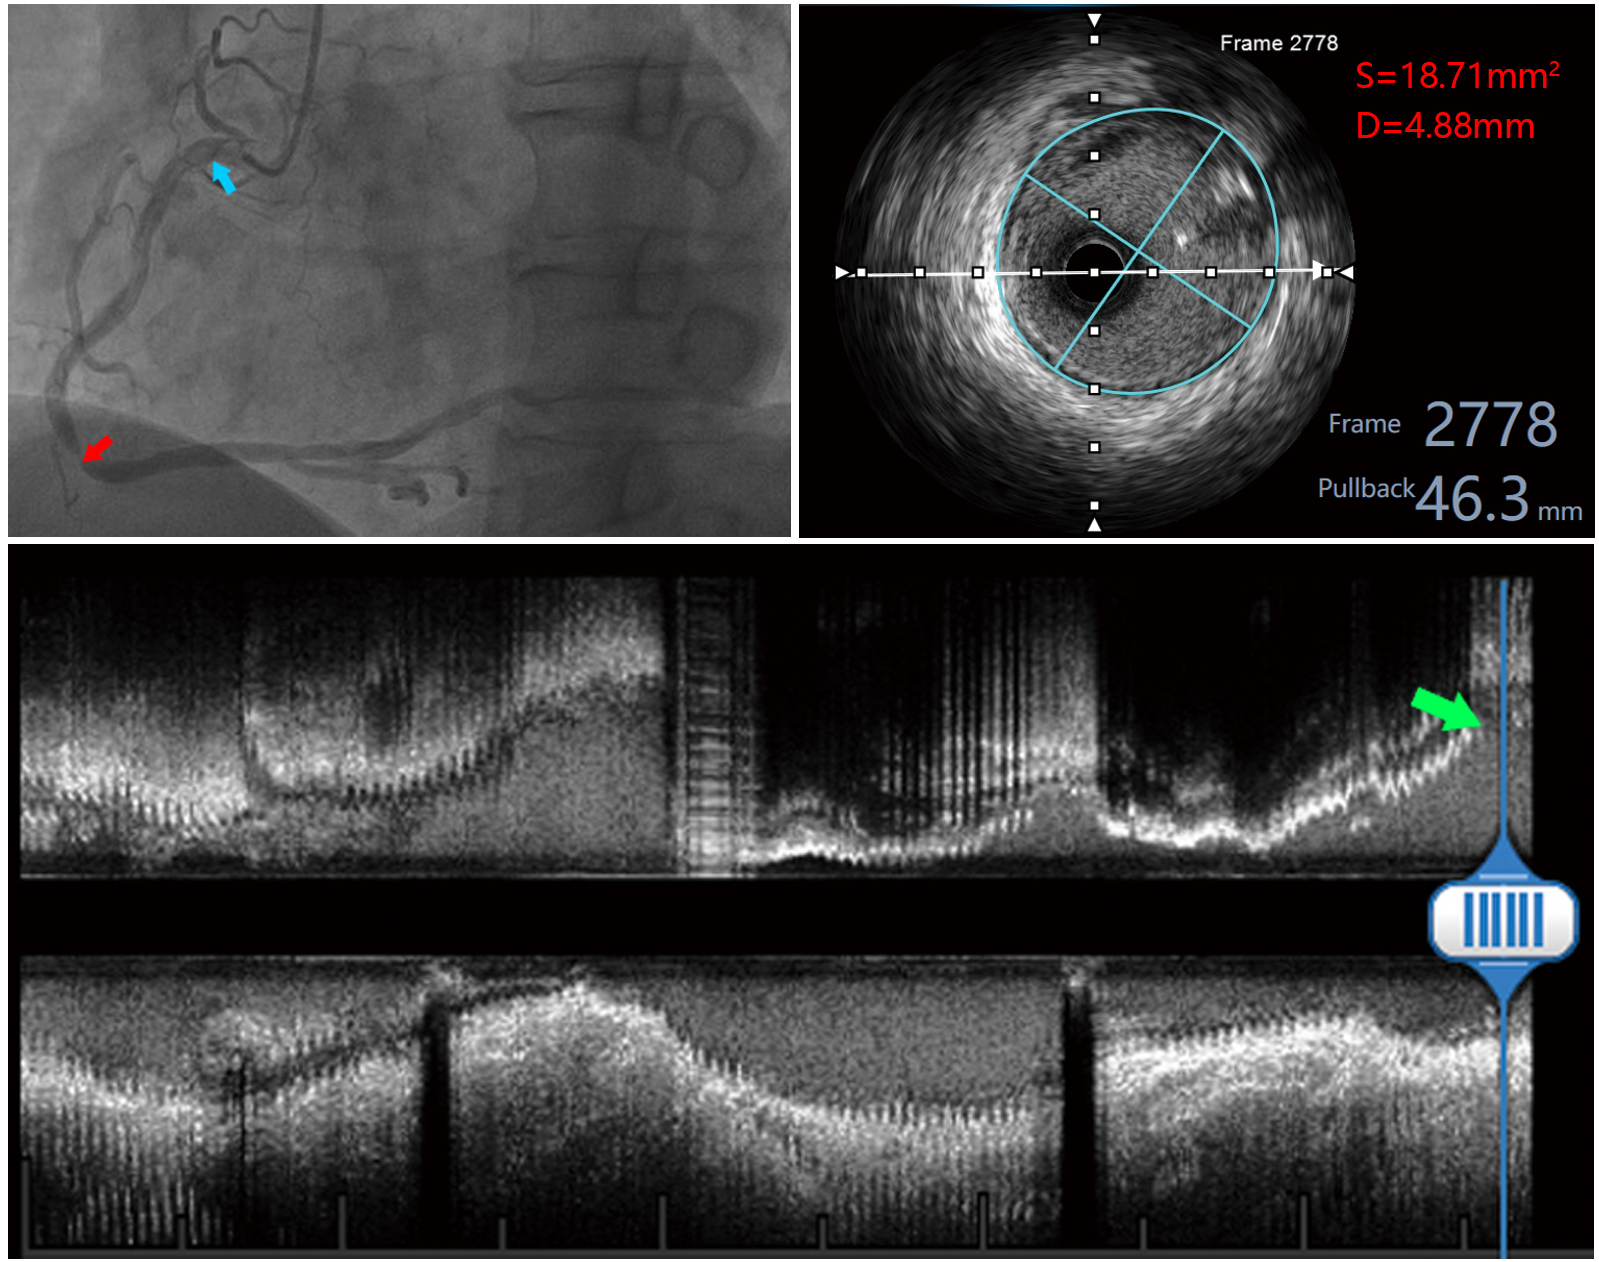

Fig. 1.Measurement image of a patient with left coronary artery lesion. The red arrow in the upper left panel indicates the anterior descending branch lesion, and the blue arrow indicates the measurement site of the left main stem; the upper right panel shows the measured area and diameter within the EEM of the left main stem; the lower panel shows the long-axis image of the left coronary artery, and the green arrow indicates the measurement site.